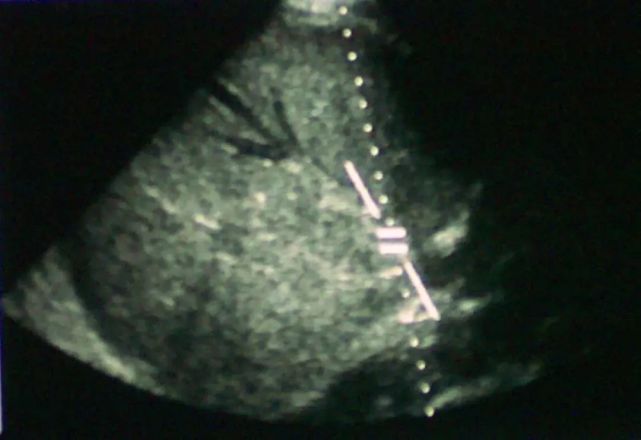

多普勒超声是首选,对于有检验的超声医生,检测静脉梗阻的灵敏度接近85%-95%。当下腔静脉闭塞引起布加综合征时,下腔静脉管腔内可见到引起管腔阻塞的物质(血栓或肿瘤)(见图1)。当怀疑BCS,肝静脉未显示或显示不清时,诊断应慎重。有些患者肝静脉未显示或显示不清,而事实上其静脉可能畅通或正常;而另一些患者,位于肝脏深处的肝静脉畅通,同一静脉又在近隔膜处闭塞。美国盐湖城Utah大学放射学教授William J. Zwiebel等认为,只有证实较大的肝静脉确实畅通,才能排除BCS。

图片

图1 超声显示肝静脉血栓,新血管形成(来源:Medscape)